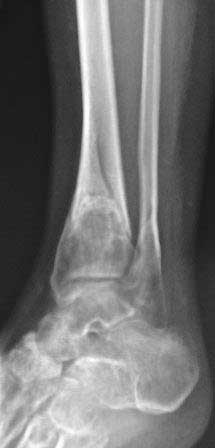

[Ortho] Вялоконсолидирующаяся перелом дистального метадиафиза костей левой голени

Пациентка 32 года, травму получила в результате ДТП, лечилась в гор.б-це №? Москвы с 19.07.по04.08.11г скелетным вытяжением, после наложена гипсовая повязка,(р-снимок 1,2.) после спадения отека гипс переведена в циркулярную, (видимо на другой вид лечения не хватило средств), гипс снят 19.11.11г(снимок-3)

.Жалобы на боли при ходьбе через несколько шагов, увеличение отека в голени и г/стопном суставе, боли ноющего и неприятного характера, хромота, при осмотре отечность голени в с-н/з и г/с суставе, при пальпации умеренная болезненность в н/з голени, подошвенное сгибание в г/с суставе ограничена и болезненна. Работа связана с ходьбой, просить помочь чтобы не потерять работу. Пока в голове только КДО аппаратом Илизарова, уважаемые коллеги  помогите советом! Доступно БИОС, пластины DCP. и прилагается последние р-снимки.